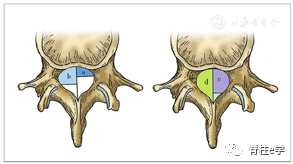

(四)腰椎间盘突出症的区域定位

根据椎间盘突出的病理和程度(CT或MRI),突出椎间盘组织在矢状面、水平面和冠状面均有相应的位置。(1998年,中国学者胡有谷提出)。

2.水平面:

以椎体后缘为界分1~4区,两侧椎弓根内界为1、2区,中1/3为1区(中央区),左右1/3为左右侧2区(旁中央区),椎弓根内外侧之间为3区(外侧区),椎弓根外侧以外为4区(极外侧区)。

3.冠状面:

将骨性椎管矢状径分为四等份,从前至后一至四份分别命名为a域、b域、c域、d域。